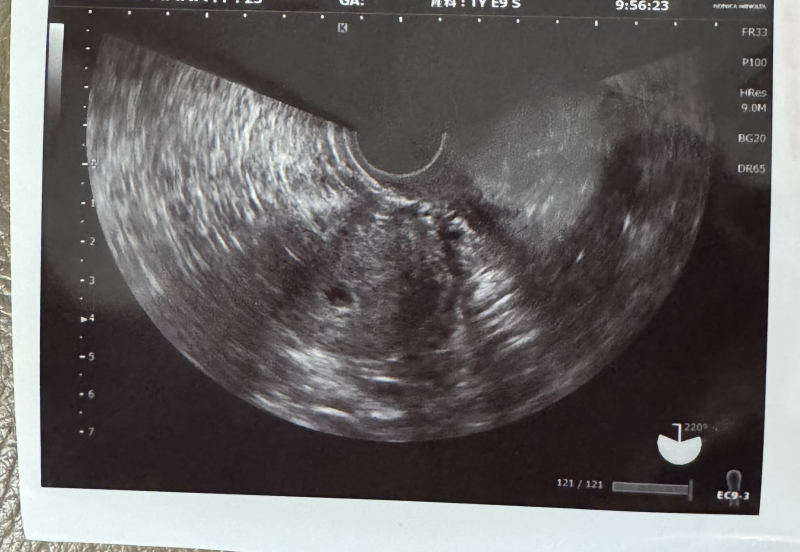

やっと胎嚢が見えた。血中hcg3421

1.2週間後に心拍確認しましょうといわれた。

だが、生理周期を28日とした場合10月4日時点だと

妊娠7週と2日。それにしては、胎嚢が小さいのと血中hcgの増え方が、ゆっくりなのが気になると言われました。